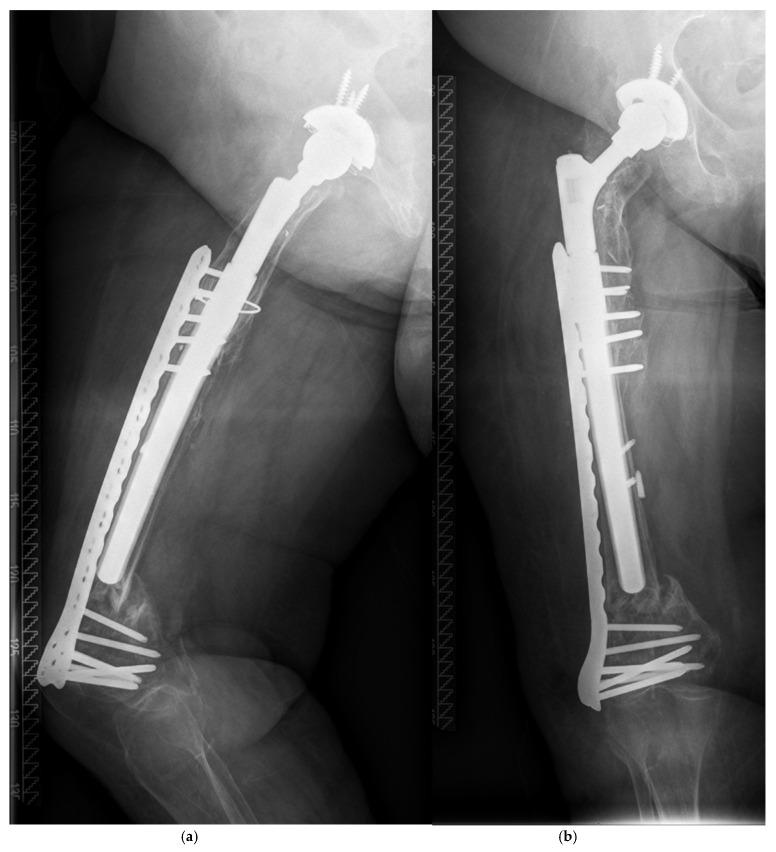

Implantation of modularly built-up stems with a tapered and fluted design is currently state of the art in revision total hip arthroplasty (RTHA). Nevertheless, implant-specific major complications like breakage of taper junctions as well as periprosthetic fractures (PPFs) may lead to failure of reconstruction during follow-up. A cohort of 117 cases receiving femoral RTHA by a modular stem was investigated retrospectively with a mean follow-up of 5.7 (0.5-13.7) years. Cumulative risk and potential factors affecting the occurrence of PPFs were calculated with the Kaplan-Meier method. In addition, cases were presented to discuss operative treatment options. A cumulative risk of PPF of 12.1% (95% CI: 0-24.6%) was calculated at 13.7 years. Female patients had significantly higher risk compared to male patients (0% after 13.5 years for male patients vs. 20.8% (95% CI: 0.5-41.2%) after 13.7 years for female patients; log-rank = 0.0438) as all five patients sustaining a PPF during follow-up were women. Four fractures were treated by open reduction and internal fixation. Non-union and collapse of the fracture occurred in one patient after closed reduction and internal fixation. Postoperative PPF after femoral revision with a modular stem has shown to be a frequent complication within this mid-term follow-up. Female patients were at a significantly higher risk in this aged cohort, indicating osteoporosis as a risk factor. The surgical treatment of PPF with an integrated long-stemmed prosthesis is challenging and thorough considerations of adequate operative treatment of PPFs are strongly advised in order to limit complication rates.

在翻修全髋关节置换术(RTHA)中,植入具有锥形和带槽设计的模块化组装柄目前是最新技术。然而,特定植入物的主要并发症,如锥形连接处断裂以及假体周围骨折(PPF),可能导致随访期间重建失败。对117例接受模块化柄股骨RTHA的病例进行了回顾性研究,平均随访5.7(0.5 - 13.7)年。采用Kaplan-Meier方法计算PPF发生的累积风险和潜在影响因素。此外,还展示了病例以讨论手术治疗方案。在13.7年时计算出PPF的累积风险为12.1%(95%可信区间:0 - 24.6%)。女性患者的风险显著高于男性患者(男性患者13.5年后为0%,而女性患者13.7年后为20.8%(95%可信区间:0.5 - 41.2%);对数秩检验 = 0.0438),因为随访期间发生PPF的所有5例患者均为女性。4例骨折采用切开复位内固定治疗。1例患者在闭合复位内固定后发生骨折不愈合和塌陷。在本次中期随访中,模块化柄股骨翻修术后的术后PPF已显示为常见并发症。在这个老年队列中,女性患者的风险显著更高,表明骨质疏松是一个风险因素。采用一体式长柄假体对PPF进行手术治疗具有挑战性,强烈建议对PPF的适当手术治疗进行全面考虑,以限制并发症发生率。